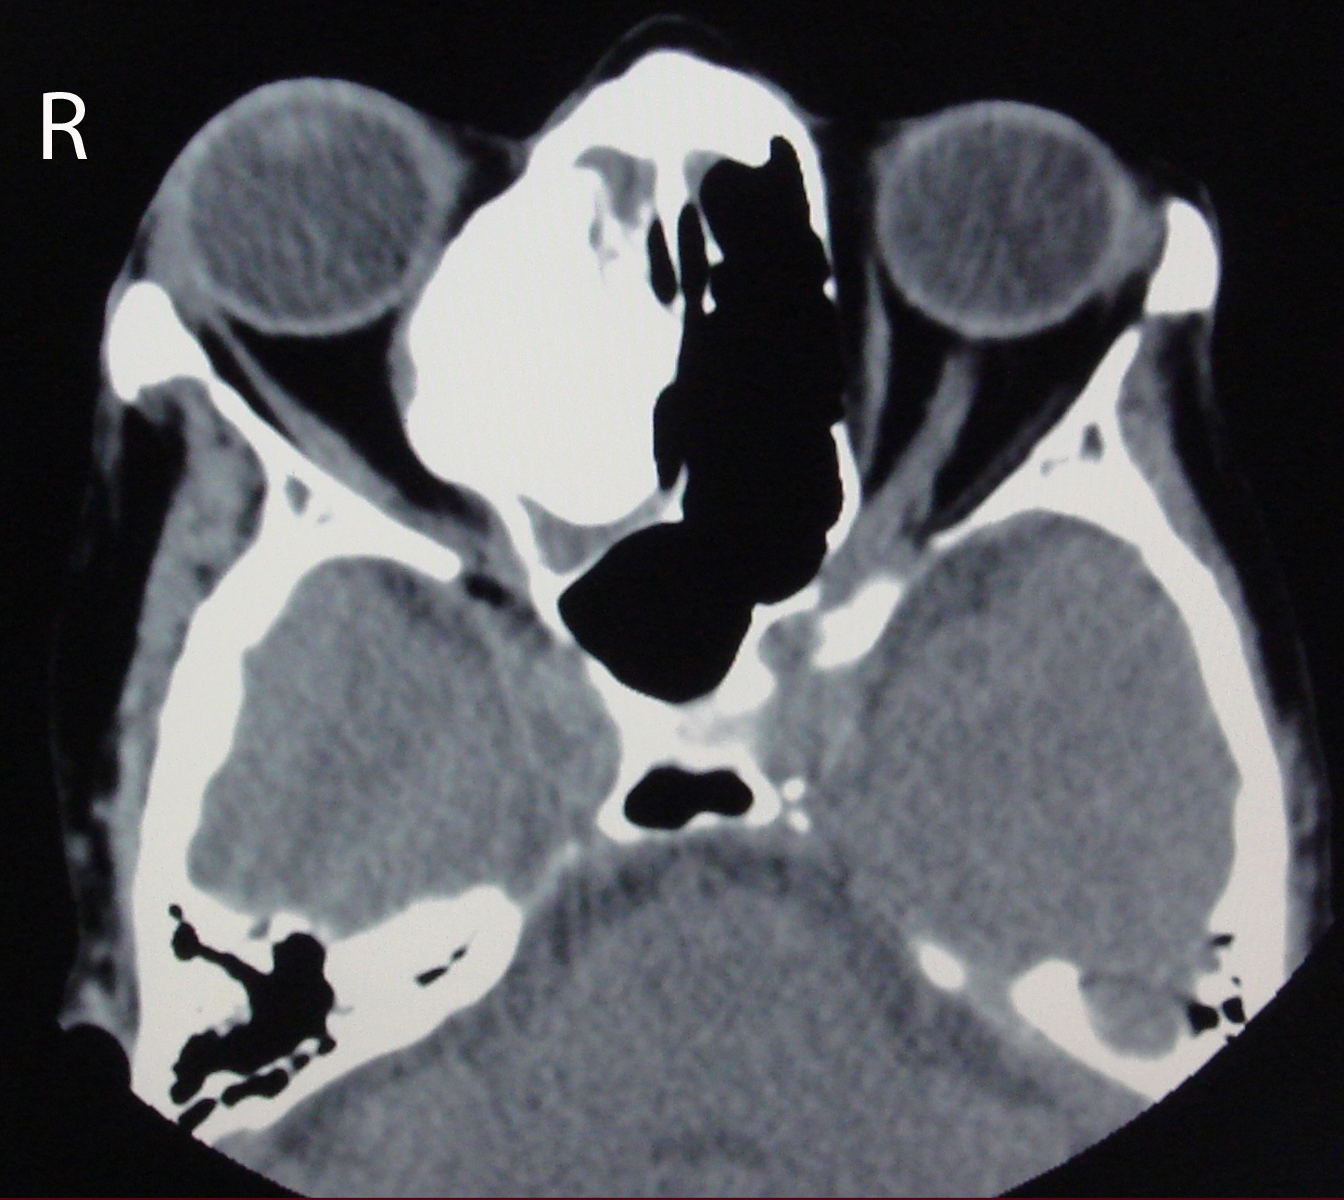

Osteoma is the most frequent benign tumor of paranasal sinuses. Usually osteomas are asymptomatic and discovered incidentally during radiological imaging for other reasons. A giant osteoma with intraorbital extension is rare. Plain radiograph may be useful; however CT scan is the best modality of investigation for diagnosing and treatment planning. In asymptomatic osteomas, serial follow-up can be done. Surgery is performed in the presence of symptoms and signs. We report a case of 60 years old woman with a large osteoma of right ethmoid sinus extending into the ipsilateral orbital cavity.